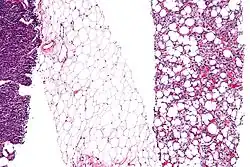

Se ha probado que células madre mesenquimales —originarias de la médula ósea— al ser puestas en sustratos con la misma rigidez que la matriz cerebral o muscular, desarrollan propiedades similares a las de esos tipos celulares.[10]